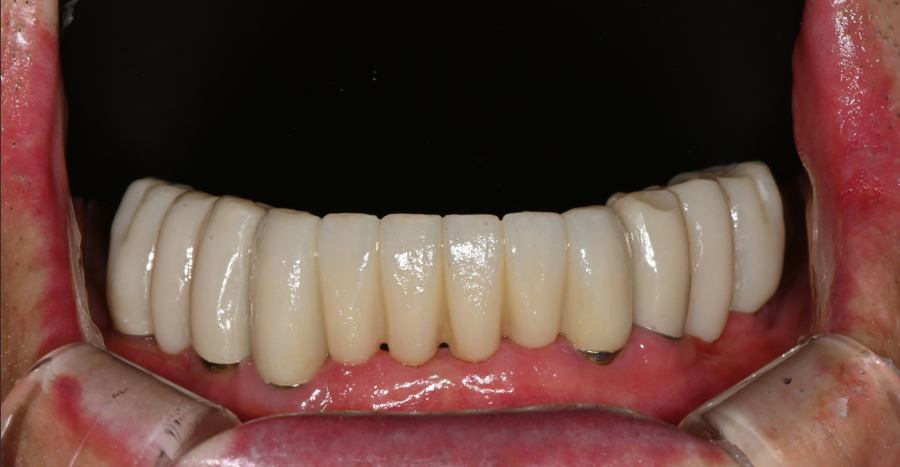

최종 오브제로 라미네이트 장착 (OVZERO)

기공소에서 완성된 최종 라미네이트는

자연광처럼 은은한 투명감과 생치에 가까운 질감,

그리고 시니어 환자분의 입술 라인과

자연스럽게 어울리는 형태로 제작되었습니다.

장착 후 환자분은 거울을 보며

“10년은 젊어진 것 같다”며 환하게 웃으셨습니다.

특히 앞니가 밝아지니

얼굴 전체가 부드럽고 환한 인상으로 바뀌었습니다.

치료 후 변화

3주 뒤 재내원하셨을 때,

잇몸은 안정적으로 적응되어 있었고

발음이나 음식 섭취에서도 불편함이

전혀 없었습니다.

가족분들도 “훨씬 어려 보인다”고 할 정도로 인상이 한층 환해졌다고 하셨습니다.